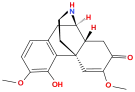

Oripavine derivatives

Structures

| Oripavine derivatives | ||||

|---|---|---|---|---|

7-PET 7-PET |

Acetorphine Acetorphine |

Alletorphine Alletorphine |

BU-48 BU-48 |

Buprenorphine Buprenorphine |

Cyprenorphine Cyprenorphine |

Dihydroetorphine Dihydroetorphine |

Etorphine Etorphine |

Homprenorphine Homprenorphine |

18,19-Dehydrobuprenorphine 18,19-Dehydrobuprenorphine |

N-cyclopropylmethylnoretorphine N-cyclopropylmethylnoretorphine |

Nepenthone Nepenthone |

Norbuprenorphine Norbuprenorphine |

Thevinone Thevinone |

Thienorphine Thienorphine |